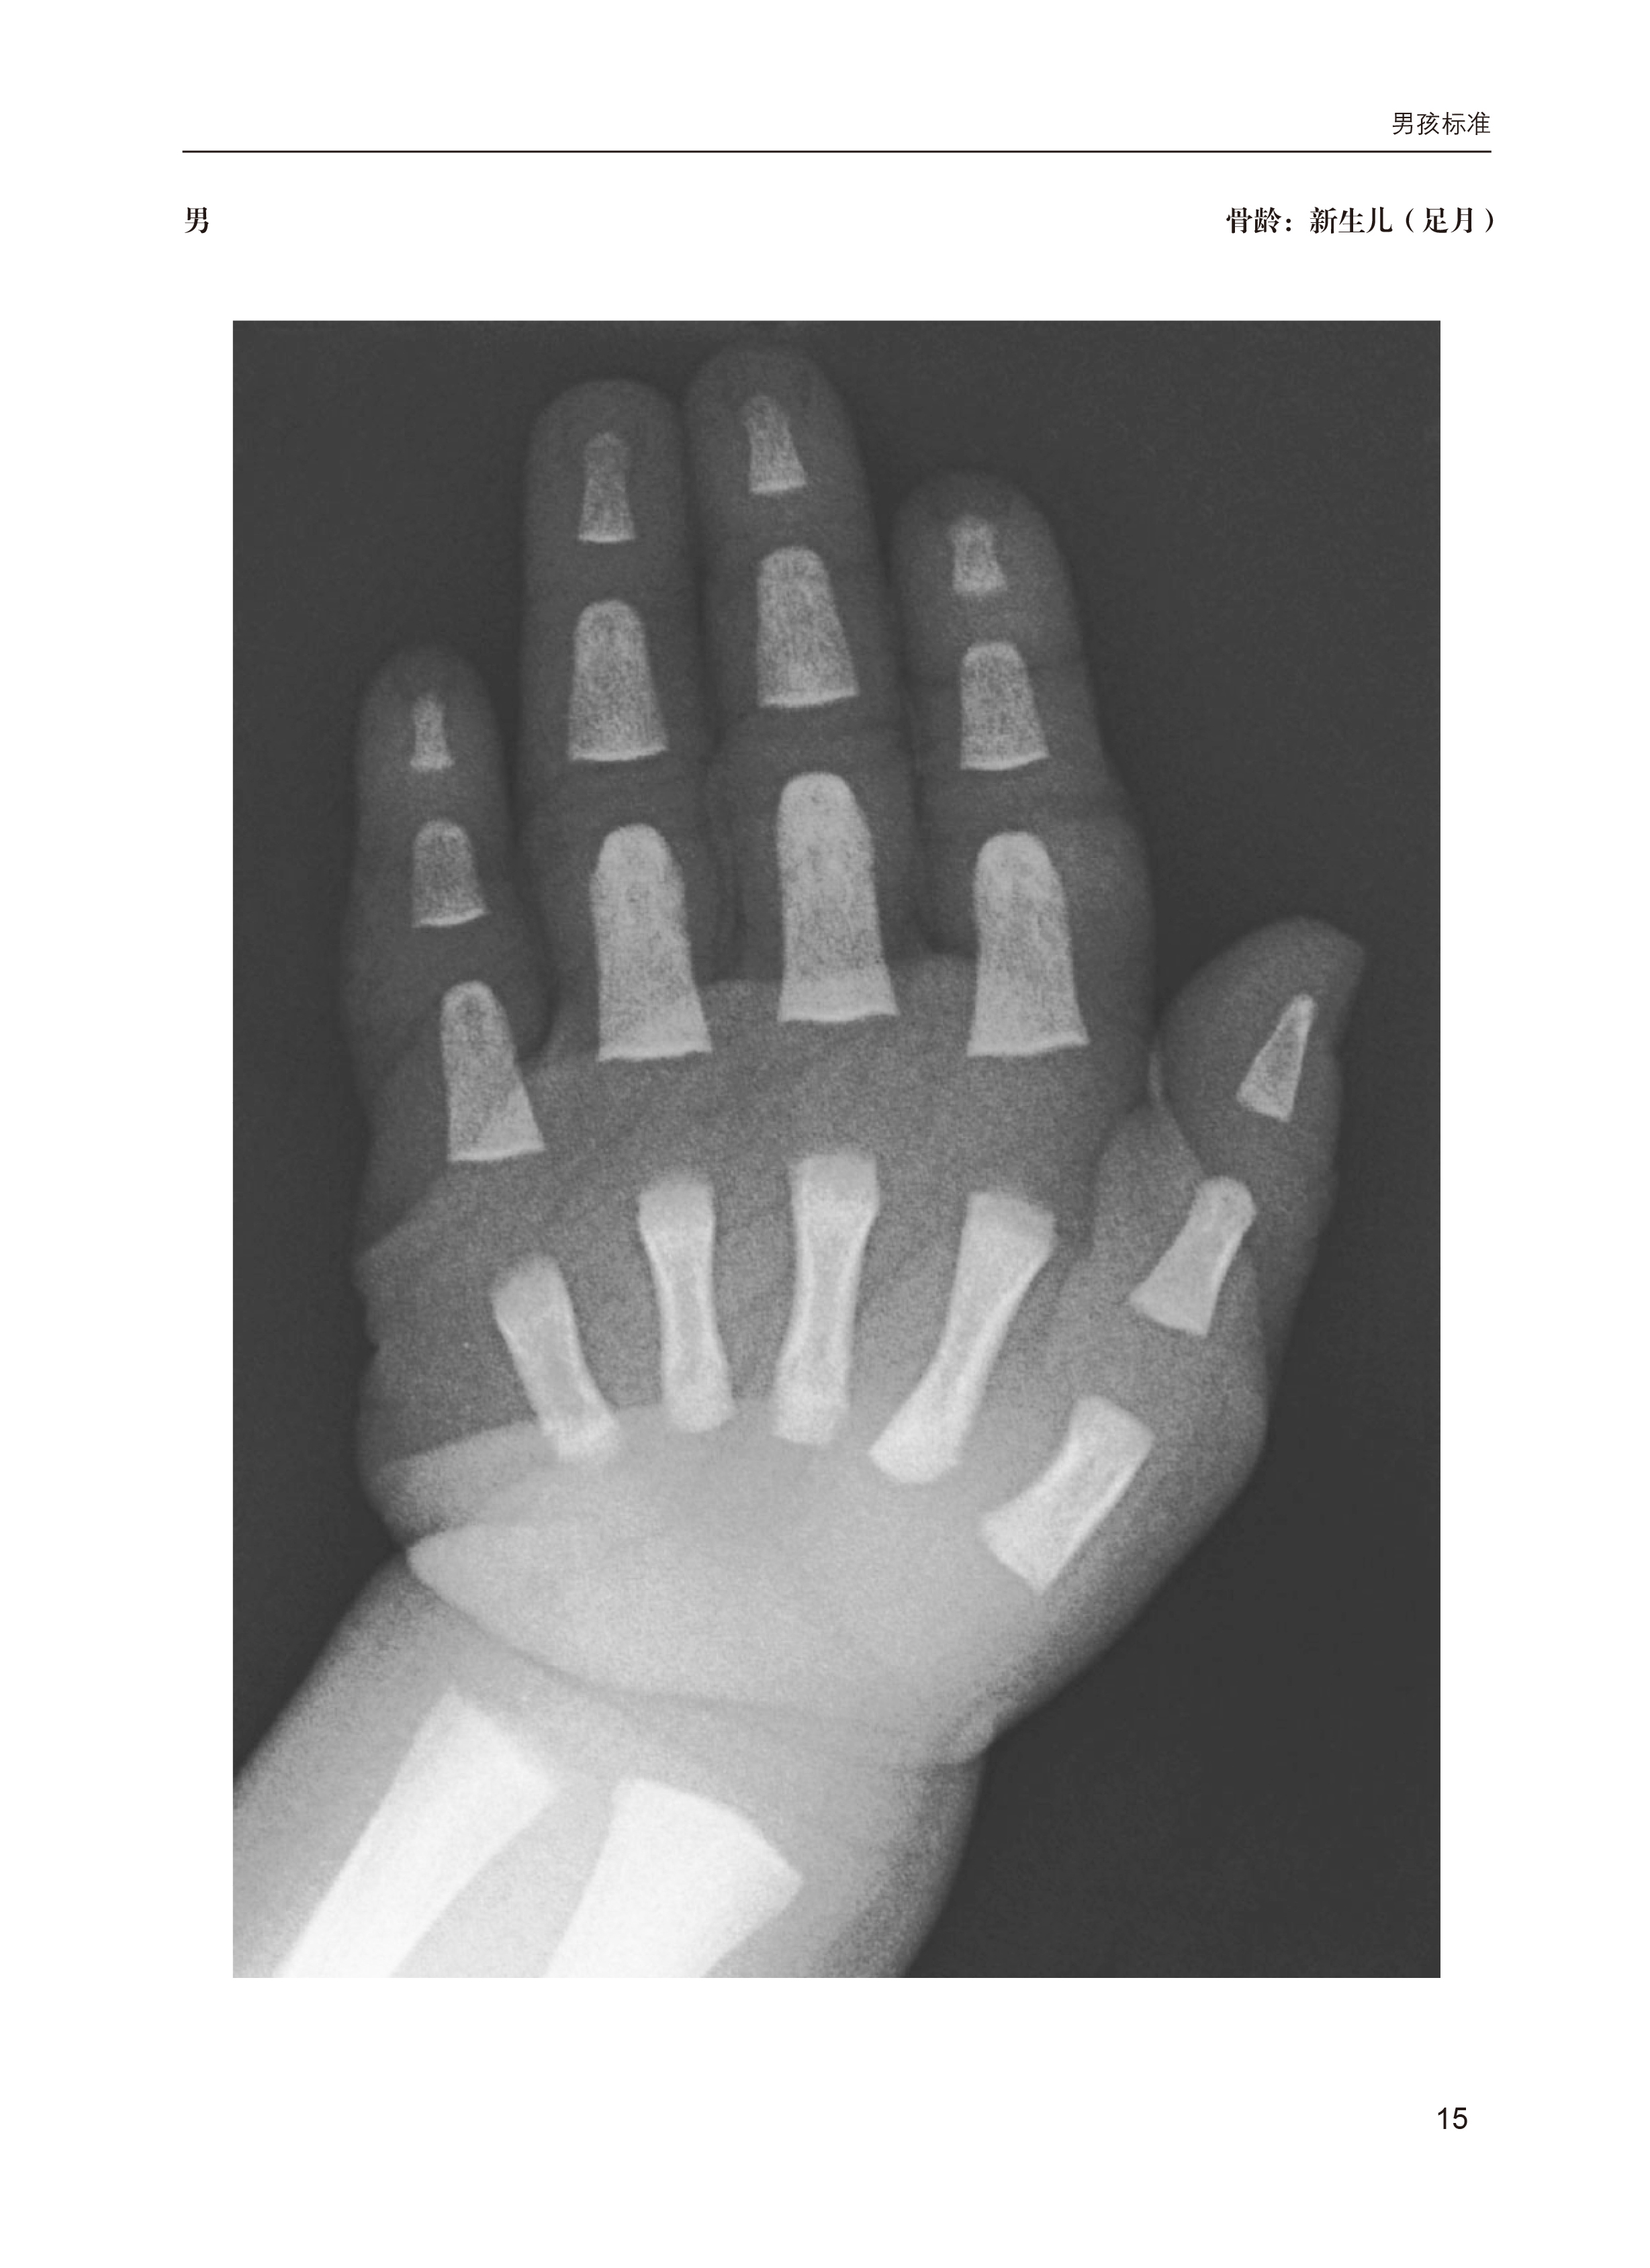

手腕部骨骼发育放射学图谱和数字化骨龄助手

主译:潘 慧 王凤丹 杜函泽

开本:850mm×1168mm 1/16

印张:9

字数:254千字

版次:2025年5月第1版 2025年5月第1次印刷

书号:ISBN 978-7-5659-3389-9

定价:68.00元